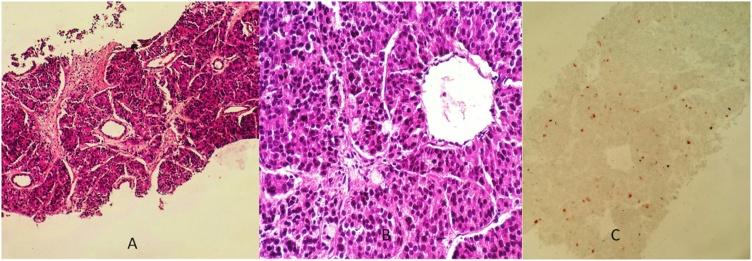

PRESENTATION OF CASE

An 85-year-old patient was complaining of lower urinary tract symptoms, and significant pelvic swelling. On physical examination, a 15-cm pelvic mass and lumpy prostate were found. Laboratory investigations revealed elevated PSA levels (PSA=300g/mL). CT scan showed a large lobulated necrotic pelvic mass and multiple swollen lymphnodes. The diagnosis of an atypical pelvic lymphoma associated with a metastatic prostate cancer was first evoked. An ultrasonography-guided biopsy of the mass was carried. The immunohistochemical study confirmed prostate adenocarcinoma. A bilateral orchiectomy was performed. A follow up of 3 months showed a decrease of PSA without shrinkage of the mass.

一名85岁患者主诉下尿路症状及明显的盆腔肿胀。体格检查发现一个15厘米的盆腔肿块和结节状前列腺。实验室检查显示前列腺特异性抗原(PSA)水平升高(PSA = 300μg/mL)。CT扫描显示一个大的分叶状坏死盆腔肿块及多个肿大淋巴结。最初考虑诊断为与转移性前列腺癌相关的非典型盆腔淋巴瘤。对肿块进行了超声引导下活检。免疫组化研究证实为前列腺腺癌。进行了双侧睾丸切除术。3个月的随访显示PSA下降,但肿块未缩小。